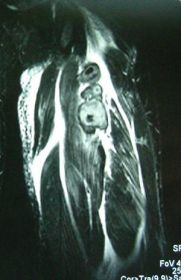

左足関節の骨棘&分離骨障害 3D-CT画像